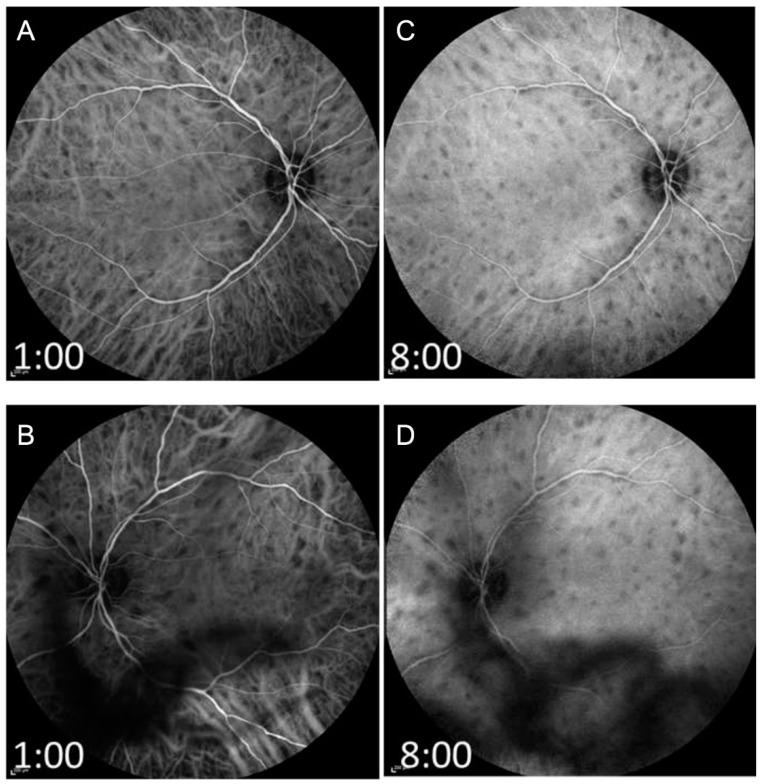

Retinal vasculitis is characterized by inflammatory involvement of retinal arterioles, venules and/or capillaries and can be associated with a myriad of systemic and ophthalmic diseases. In this review, we have comprehensively discussed the etiologies, clinical manifestations, and presentations of retinal vasculitis. We have also included newer advances in imaging in retinal vasculitis such as OCTA and widefield imaging.

视网膜血管炎的特征是视网膜小动脉、小静脉和/或毛细血管发生炎症,并且可能与多种全身和眼科疾病相关。在本综述中,我们全面讨论了视网膜血管炎的病因、临床表现和症状。我们还纳入了视网膜血管炎成像方面的最新进展,如光学相干断层扫描血管造影(OCTA)和广角成像。